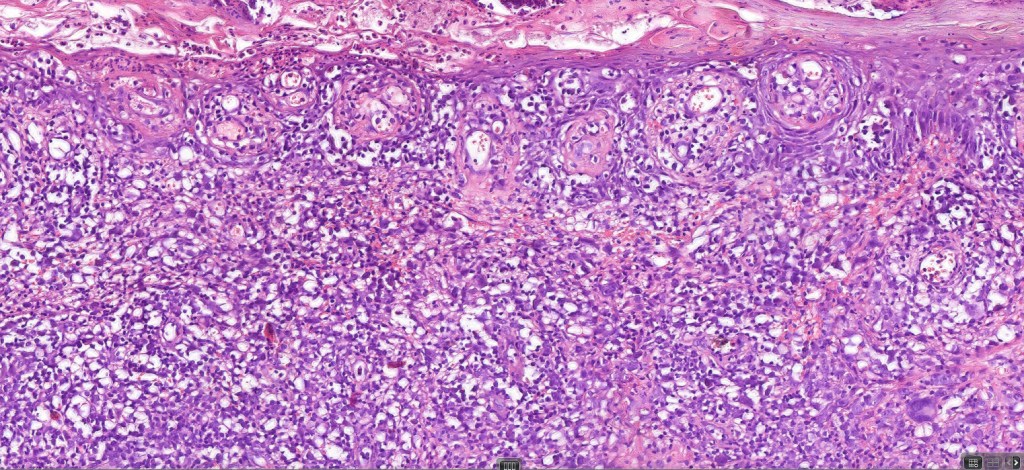

Histological features

The histological hallmark of mycosis fungoides is the presence of large atypical lymphocytes with a convoluted/cerebriform nuclear border (Sézary cells). These may be found at the epidermal-dermal jnuction and as collections within the epidermis (Pautrier microabscess). These are most easily found in plaque stage disease. The epidermal component can be subtle in patch stage disease and is often lost in tumor stage dsease. The classification into patch, plaque & tumor stage disease is less helpful histologically as the features merge from one to the other. It is all a matter of degree.

Plaque Stage Disease

•Compact hyperkeratosis & patchy parakeratosis

•Acanthosis

•Psoriasiform hyperplasia common

•Epidermotropism is often marked with conspicuous Pautrier microabscesses

•Lichenoid variant & poikiloderma atrophicans vasculare

•Variable folliculotropism (+/- mucinosis) & syringotropism

•Coarse collagen bundles in papillary dermis

•Superficial band-like dermal infiltrate of atypical lymphocytes, eosinophils, plasma cells & histiocytes

Tumor Stage Disease

•Epidermotropism is often minimal or absent

•Dense, broad diffuse or nodular, dermal infiltrate often extending into the subcutaneous fat